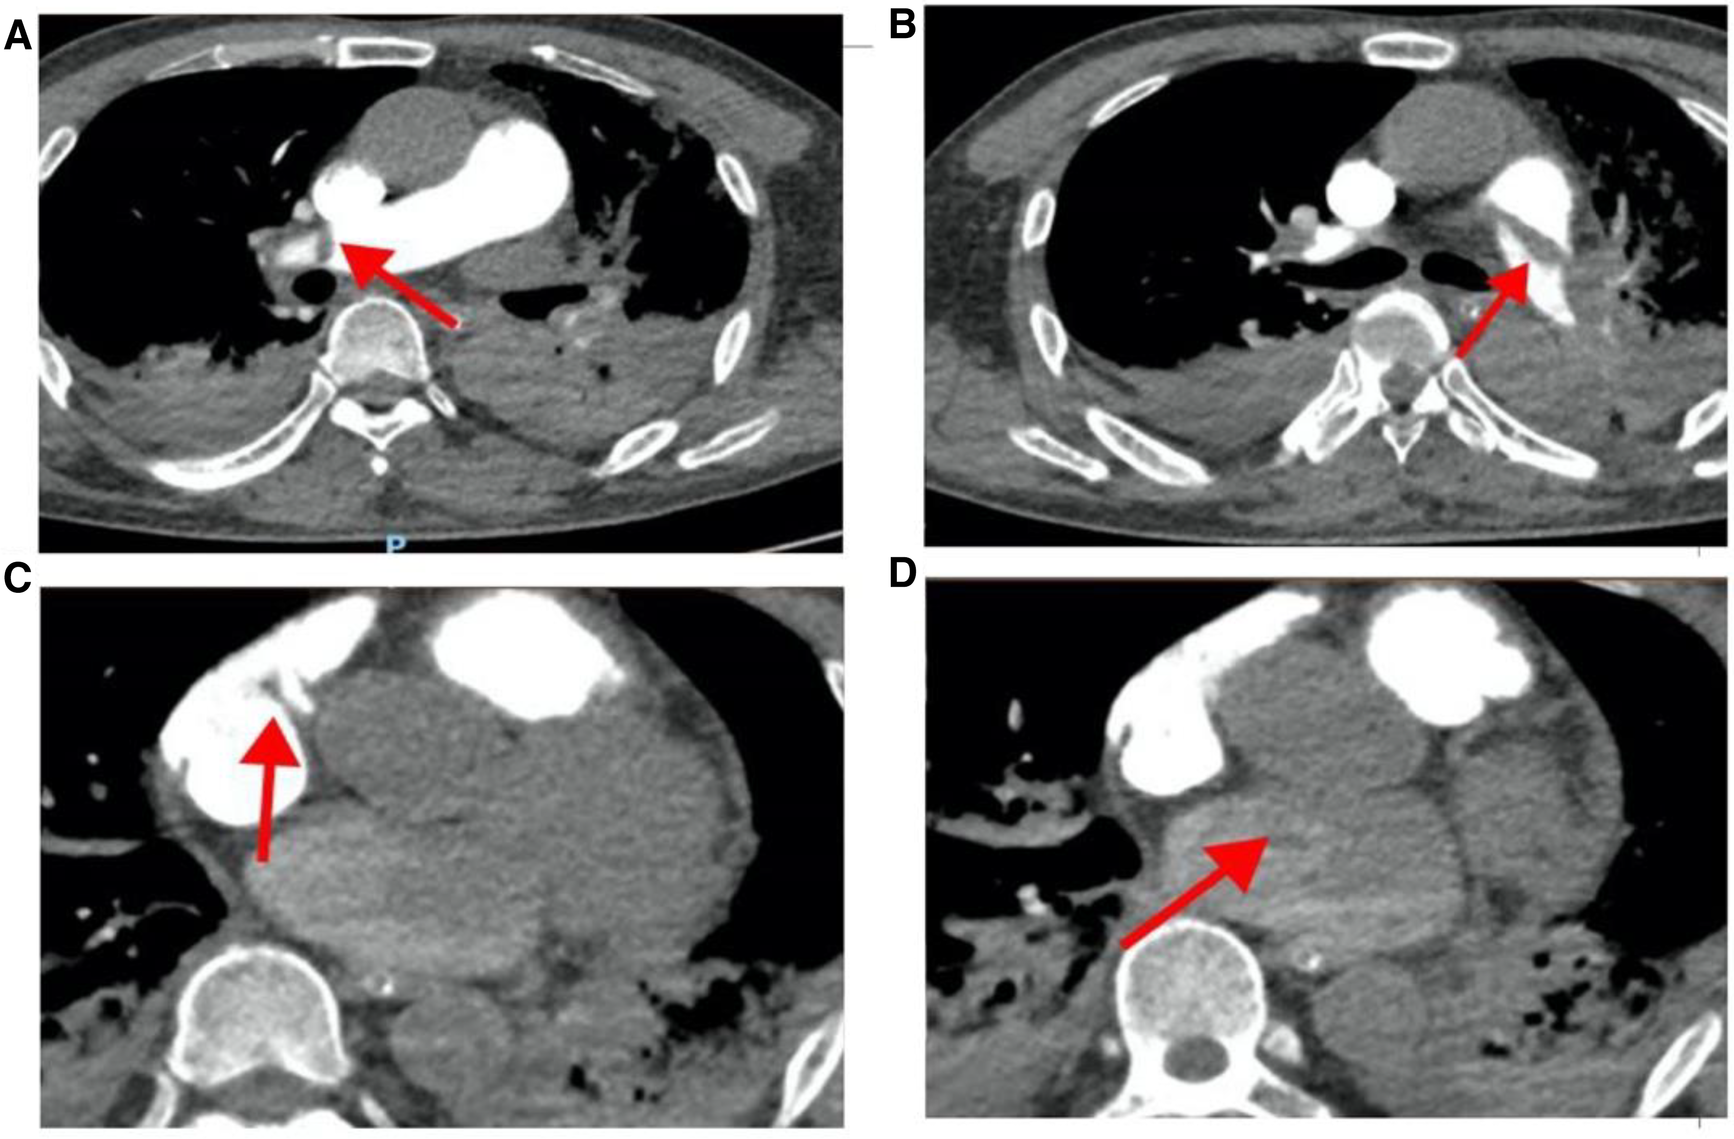

On March 28, 2023, at 14:20, the patient was transferred to our hospital's Intensive Medicine Department. The patient had a temperature of 36°C, a pulse of 98 beats/min, a respiratory rate of 20 breaths/min, and blood pressure of 92/62 mmHg (under the combined auxiliary treatment with norepinephrine, epinephrine, and dobutamine), Vasoactive Inotropic Score (VIS): 105 points. Pulse oxygen saturation (SpO2) was 99%. Blood gas analysis showed a pH of 7.49, blood oxygen concentration of 50%, carbon dioxide partial pressure of 26.00 mmHg, oxygen saturation of 99%, oxygen partial pressure of 106.00 mmHg, blood lactate level of 3.5 mmol/L, and an oxygenation index of 212.00 mmHg. The patient's laboratory test results were Creatinine 176 umol/L, D-dimer >20 mg/L, N-terminal pro-B-type natriuretic peptide (NT-proBNP) 14,535 pg/ml, and cardiac troponin I 1.12 ng/ml. The ECG results indicated a sinus rhythm, abnormal Q waves (Ⅲ, aVF), and T wave changes. Echocardiography showed a left atrial anteroposterior diameter of 26 mm, a right atrial anteroposterior diameter of 46 mm, a left ventricular end-diastolic diameter of 40 mm, a right ventricular anteroposterior diameter of 23 mm, a left ventricular ejection fraction of 54%, thrombi in both atria, severe pulmonary arterial hypertension (70 mmHg), and an atrial septal defect width of approximately 4.1 mm (Figure 2, Table 1). Thrombosis formation was seen in the bilateral popliteal veins (complete occlusion). Pulmonary artery CT angiography indicated bilateral multiple PEs and intra-atrial occupying lesions in both atria (Figure 3).

Figure 3

Pulmonary artery CT angiography results when the patient was hospitalized. (A) The red arrow points to the filling defect of the right pulmonary artery; (B) the red arrow points to the filling defect of the left pulmonary artery; (C) the red arrow points to the space in the right atrium; (D) the red arrow points to the space in the left atrium.